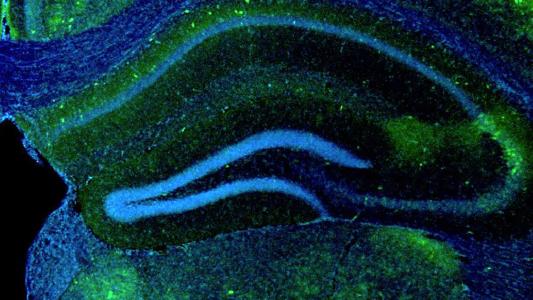

Bioengineered protein could enhance memory

Memory-related conditions are notoriously hard to treat, but there may be a way to boost recall in the brain.